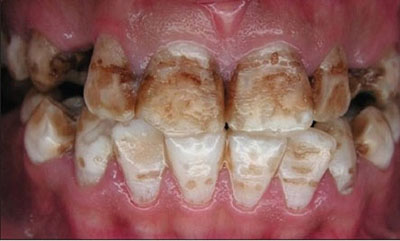

- Деструктивная — форма, при которой наблюдается нарушение коронок из-за эрозивных разрушений и стирания твёрдых тканей зуба.

- Тяжёлая: вся эмаль окрашена в жёлтый или коричневый цвет. Твёрдая часть зуба поражена ямками.

- Деструктивная. Истирание эмали, нарушение формы коронки из-за эрозий.